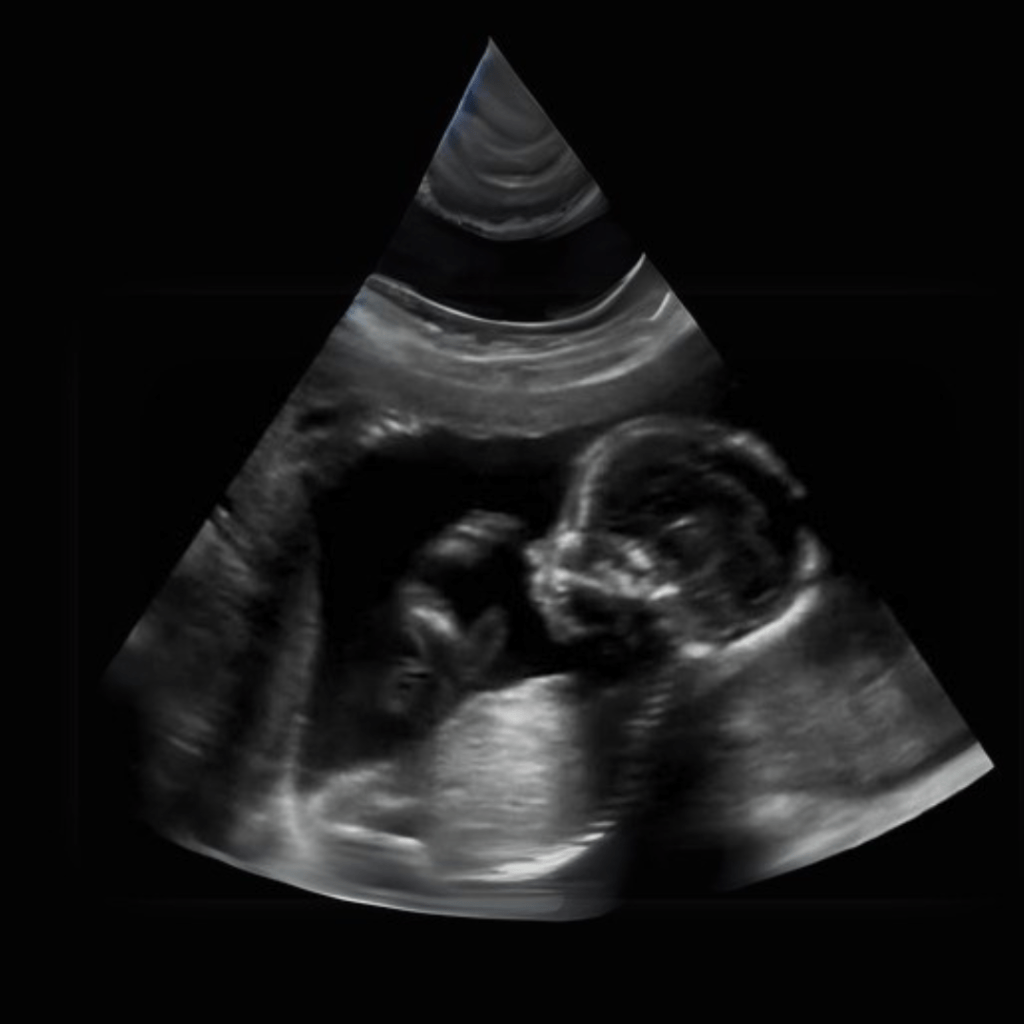

Obstetric (2D, 3D, 4D, 5D): High-definition imaging for pregnancy monitoring.